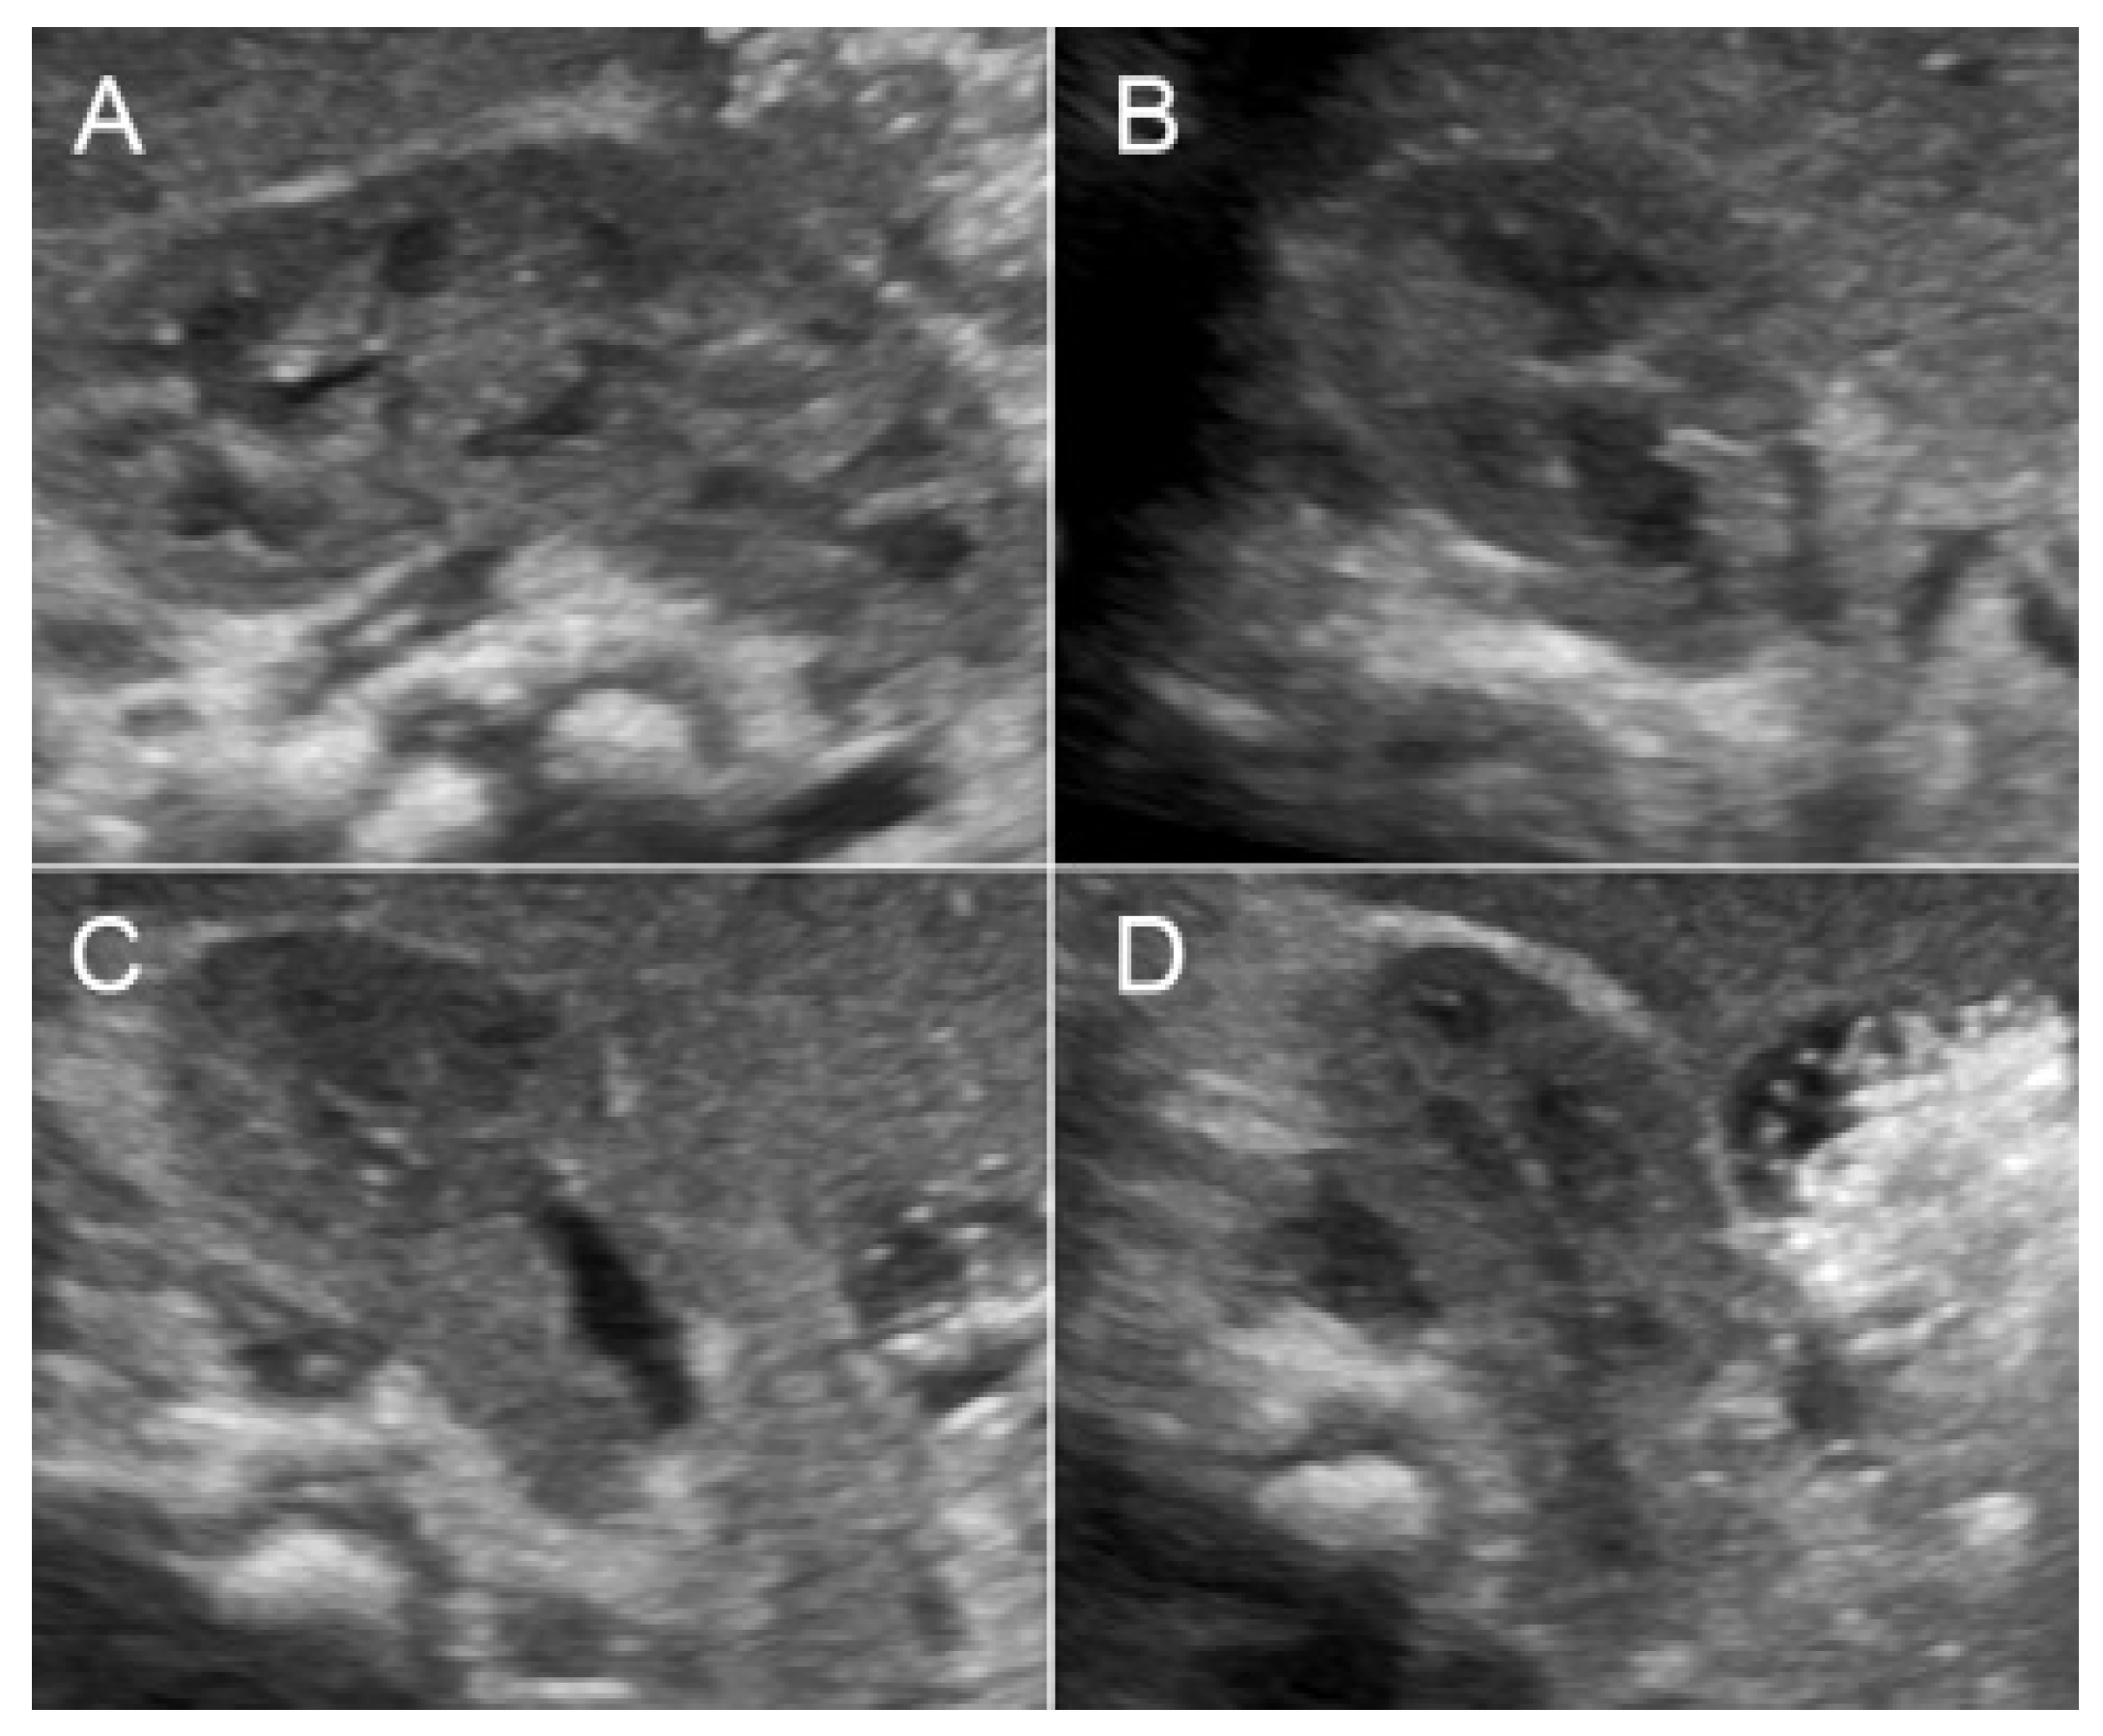

A 32-year-old pregnant woman, G4 P2102, attended her first visit of antenatal care at 23+3 weeks of gestation. Ultrasound examination for anomaly screening demonstrated cardiac defects, including double-outlet right ventricle: DORV-TOF type, with severe pulmonary stenosis (Figure 1) and left superior vena cava. Detailed ultrasound showed no associated abnormalities. Fetal biometry was consistent with gestational age except abdominal circumference and estimated fetal weight, which were relatively low (at 10th percentile), reflecting some degree of growth restriction. However, detailed ultrasound on the follow-up scans at 28 weeks of gestation showed subtle abnormalities, including malrotation of both kidneys, the hilum or renal pelvis facing posteriorly to the abdominal wall (Figure 2). Furthermore, 3D-ultrasound revealed abnormal external ear structure (markedly prominent crus of anti-helix) (Figure 3). Non-stress tests (NST) showed spontaneous fetal heart rate (FHR) accelerations (normal reactive tests) (23+3 weeks). Interestingly, the fetus showed persistent non-response to acoustic stimulation tests at 26, 30, 32, 36 and 38 weeks (no FHR accelerations as well as no quickening perceived by ultrasound) (Figure 4), probably reflective of auditory dysfunction. Based on the findings of heart defect, ear defect, renal defect and growth restriction, several differential diagnoses were listed, including CHARGE syndrome. Theoretically, fetal blood sampling for molecular genetic tests should be performed. Nevertheless, since no lethal condition was identified and the couple wanted to continue pregnancy regardless of investigation results, prenatal invasive diagnosis was avoided, and we waited for postnatal work-up instead. She had no significant underlying disease and no familial history of hereditary diseases. Her pregnancy was uneventful except that she developed gestational diabetes (GDM) at 28 weeks of gestation, which was well-controlled with diabetic diet.

Figure 2.

Malrotation of the right kidney with abnormally lateral-posterior renal pelvis (A) sagittal scan; (B–D) cross-sectional scan at upper, mid and lower portion).